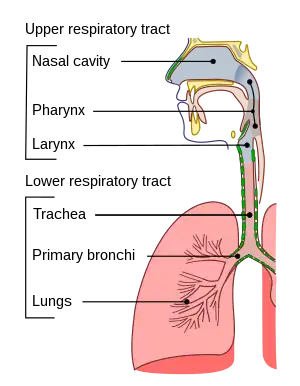

Pulmonary aspiration is the entry of material such as pharyngeal secretions, food or drink, or stomach contents from the oropharynx or gastrointestinal tract, into the larynx (voice box) and lower respiratory tract, the portions of the respiratory system from the trachea (windpipe) to the lungs. A person may inhale the material, or it may be delivered into the tracheobronchial tree during positive pressure ventilation. When pulmonary aspiration occurs during eating and drinking, the aspirated material is often colloquially referred to as "going down the wrong pipe".